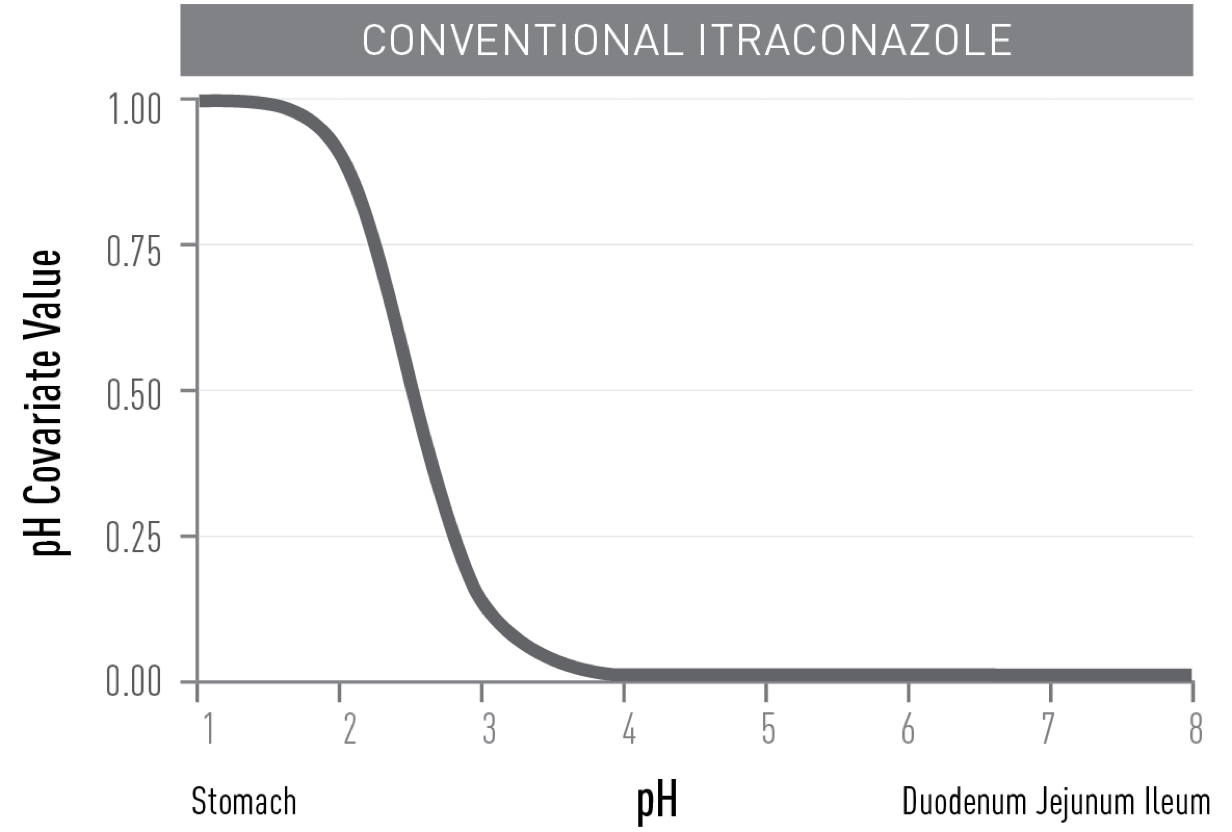

UNLIKE CONVENTIONAL ITRACONAZOLE,

TOLSURA is less soluble in the acidic environment of the stomach and soluble in the higher pH of the small intestine, resulting in improved absorption2.

- THE ABSORPTION OF TOLSURA IS NOT REDUCED† with proton pump inhibitors as the

drug is released in the small intestine5,7,8.

†Monitor for side effects as dosing with a proton pump inhibitor may increase peak and overall exposure of itraconazole